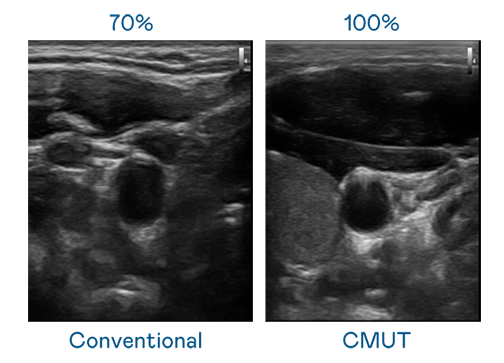

CMUT 技术是一种用电容式微机电元件来产生超音波讯号的技术。与传统 PZT 压电式技术相比,CMUT 频宽增加 30%,更宽频的超音波讯号让影像解析度大幅提升,是实现高影像品质医疗超音波扫描、促进精准医疗发展的关键技术。

大频宽带来超清晰影像

超音波影像的解析度高低,首先取决于探头能发出的讯号频宽。完美真人 CMUT 可提供高清晰的超音波讯号,提供高频宽、高灵敏度、影像纹理细节更高的超音波影像,协助医护人员缩短影像判读时间及利用精准的医疗影像进行诊断。